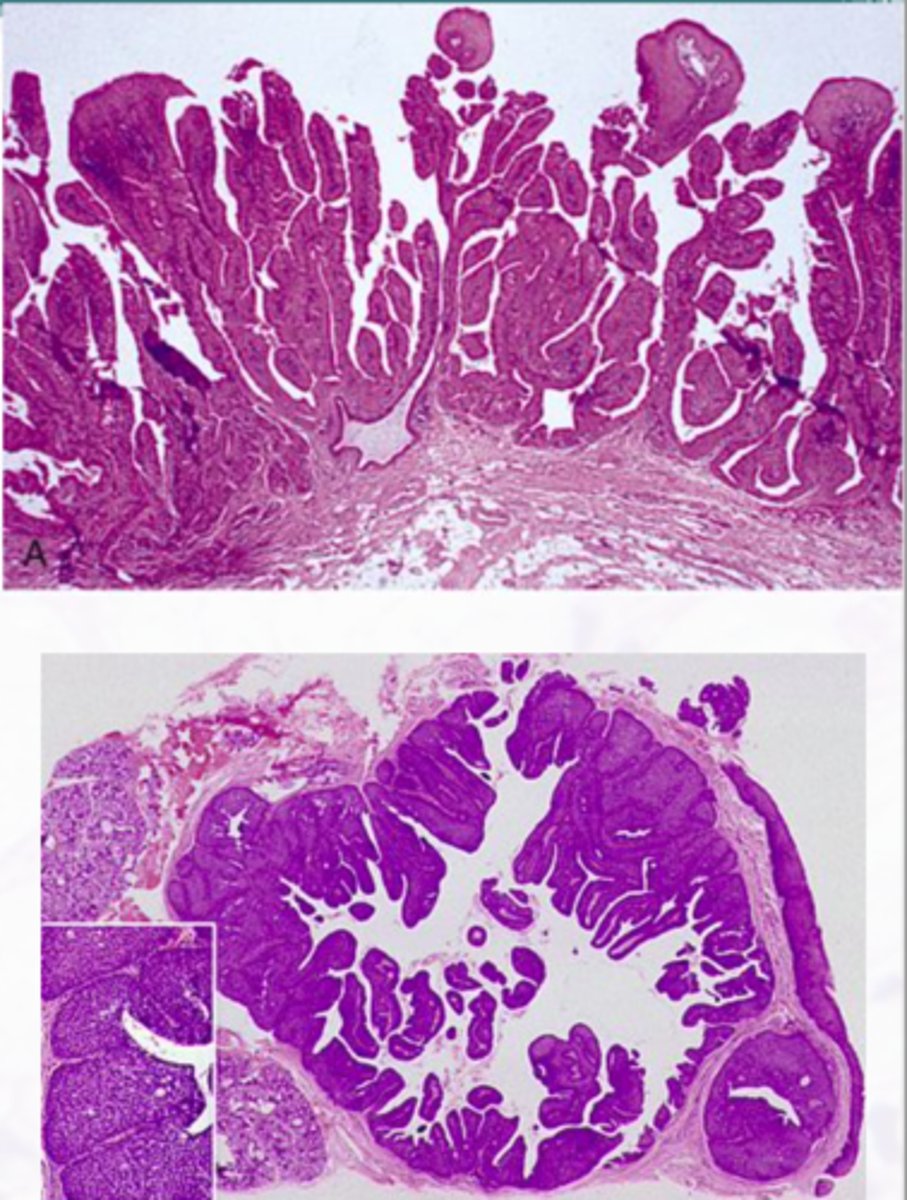

Pleomorphic Adenoma

Most common salivary gland neoplasm, Mix of epithelial and mesenchymal elements

Various patterns within the tumor, Encapsulated

Double layered ductal structures and myoepithelial cells, Stroma appears myxoid, cartilaginous, and hylanized

surgical removal (Small percentage of tumors undergo malignant transformation)

Treatment for Pleomorphic Adenoma